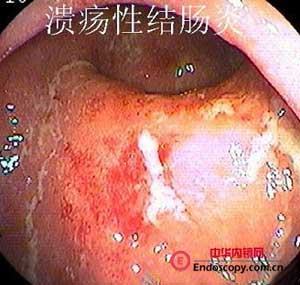

診斷上主要依靠纖維結腸鏡檢,因為約在90%~95%患者直腸和乙狀結腸受累,因此事實上通過纖維乙狀結腸鏡檢已能明確診斷。鏡檢中可看到充血、水腫的黏膜,脆而易出血。在進展性病例中可看到潰瘍,周圍有隆起的肉芽組織和水腫的黏膜,貌似息肉樣,或可稱為假息肉形成。在慢性進展性病例中直腸和乙狀結腸腔可明顯縮小,為明確病變範圍,還是套用纖維結腸鏡作全結腸檢查,同時作多處活組織檢查以便與克隆結腸炎鑑別。

慢性潰瘍性結腸炎 腸鏡表現2、黏膜活檢組織學檢查呈炎症性反應,同時可見糜爛、潰瘍、隱窩膿腫、腺體排列異常、杯狀細胞減少及上皮變化。